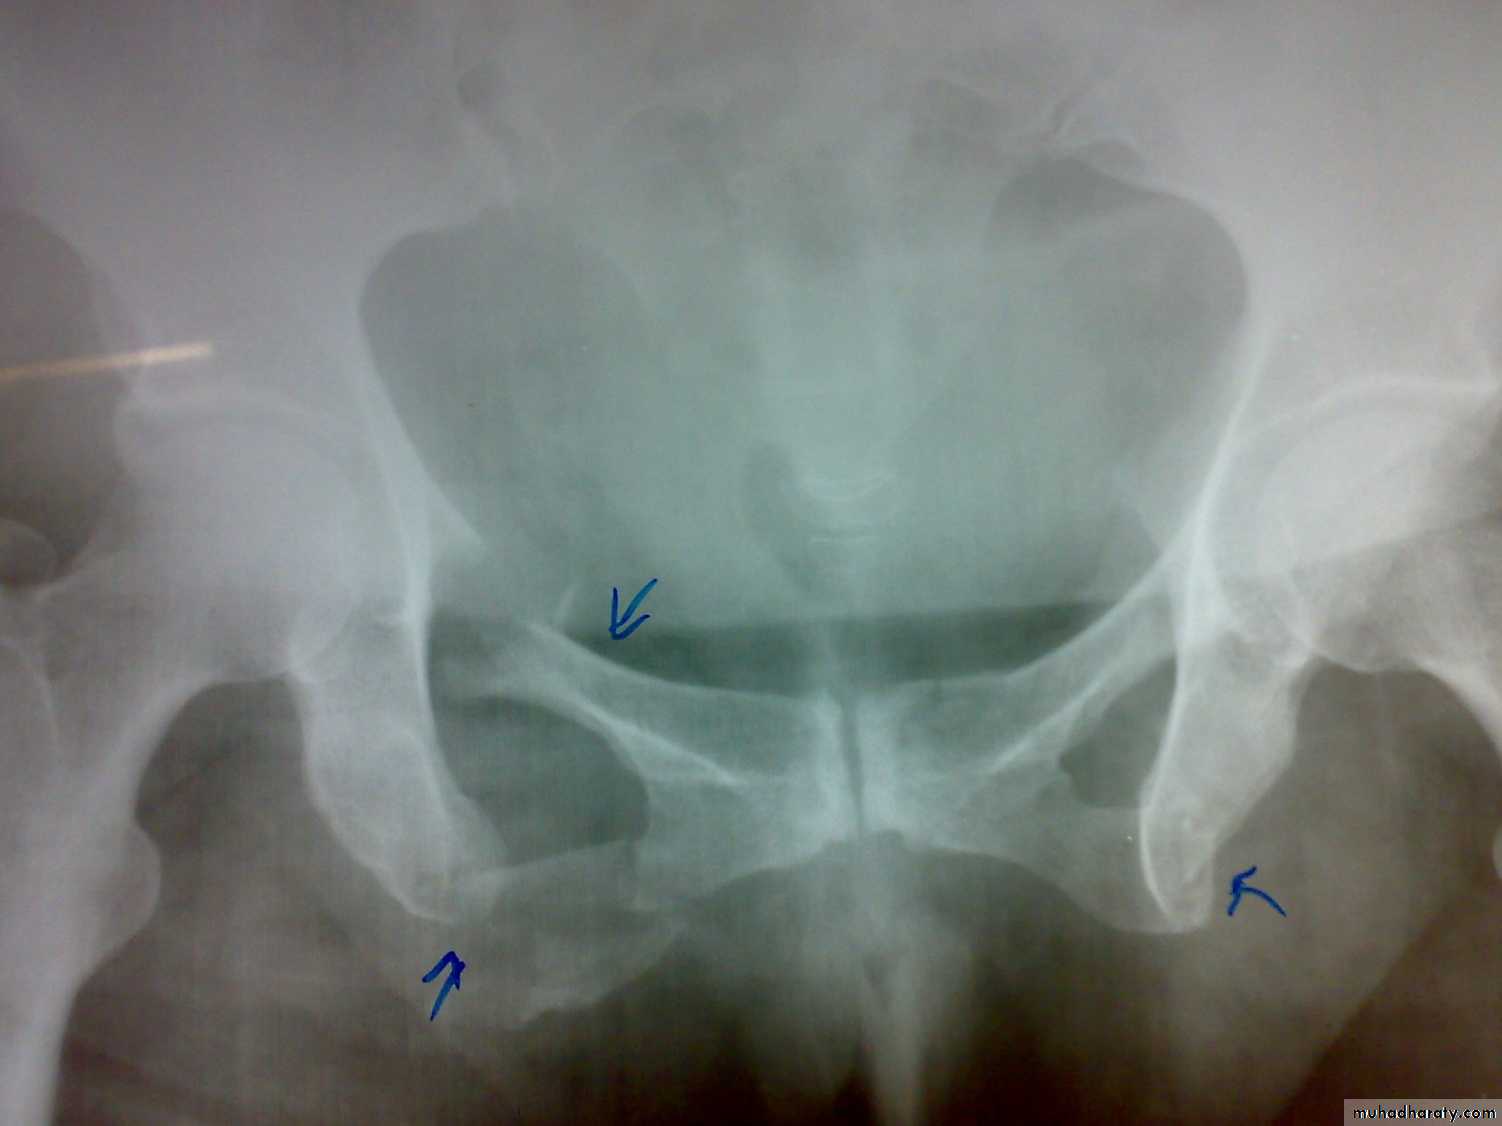

Unstable ring fractures

There are fractures around or separation of symphysis pubis or sacroiliac joint.

Types of unstable fracture pelvic ring

1- antero-posterior compression (open book).

2- lateral compression (closed book).

3- Vertical force cause vertical displacement of the innominate bone on the same side.

4- combination injuries.